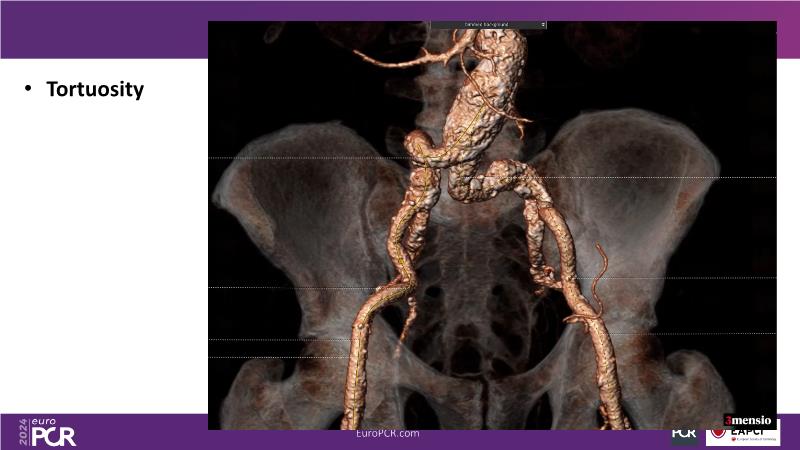

Tune in to this session for insights on optimizing vascular access and closure techniques. Explore steps like thorough CT analysis, ultrasound-guided puncture, and contingency plans for alternative access methods to minimize complications. Discover a novel patch-based closure approach offering immediate hemostasis and simplified usage, addressing issues like re-access associated with other closure technologies. Witness the effectiveness of combining suture- and plug-based closure methods for achieving excellent outcomes.